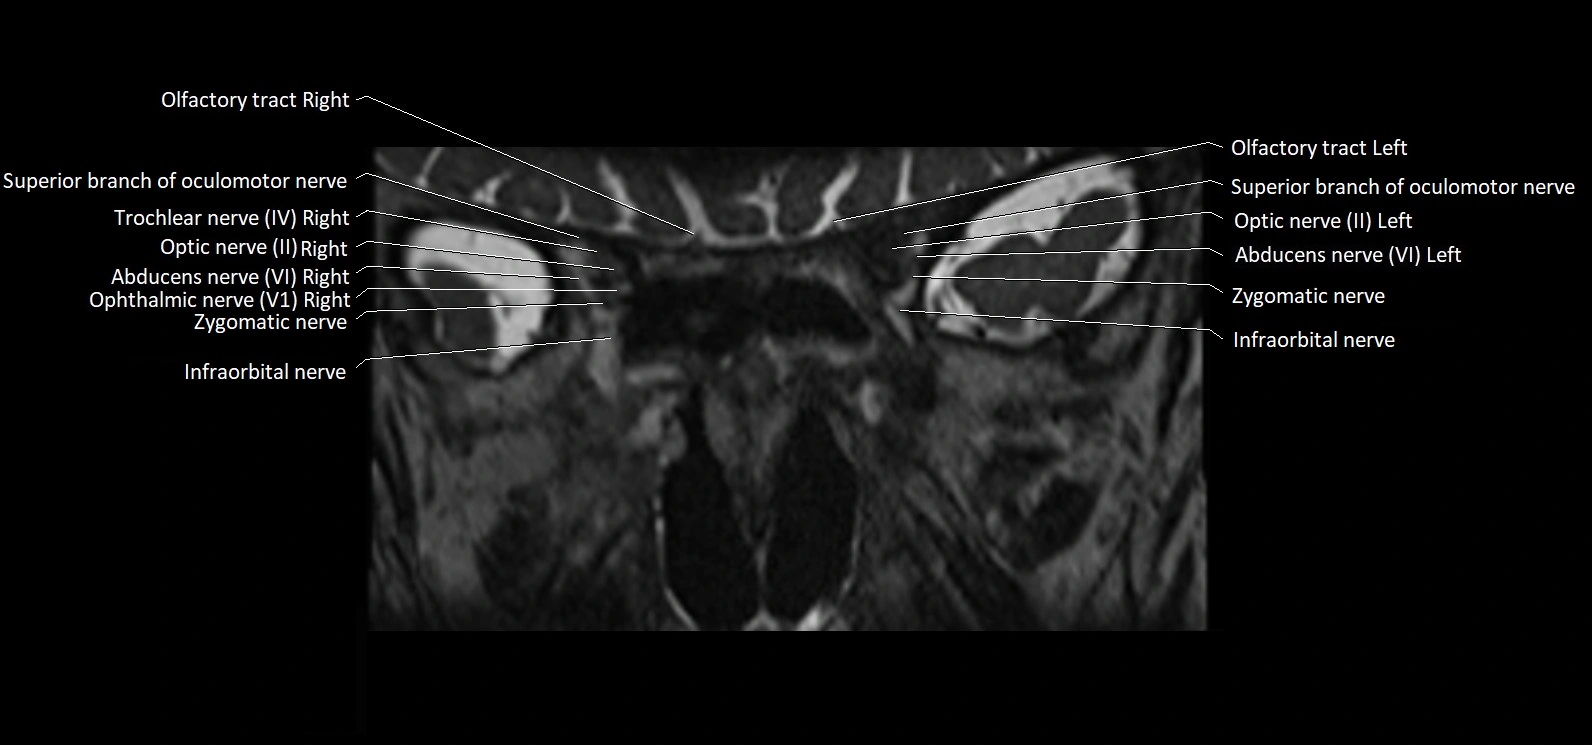

MRI Appearance

• The abducens nerve is a small, thin, linear structure

• Best visualized on high-resolution T2-weighted 3D MRI sequences (e.g., FIESTA or CISS)

• Seen as a hypointense (dark) line running from the brainstem at the pontomedullary junction, traversing the prepontine cistern, and entering Dorello’s canal under the petrosphenoidal ligament, then into the cavernous sinus, and finally the orbit

• May be challenging to visualize in standard MRI due to its small size

• Pathology may be inferred by absence, displacement, or enhancement of the nerve

MRI images

image